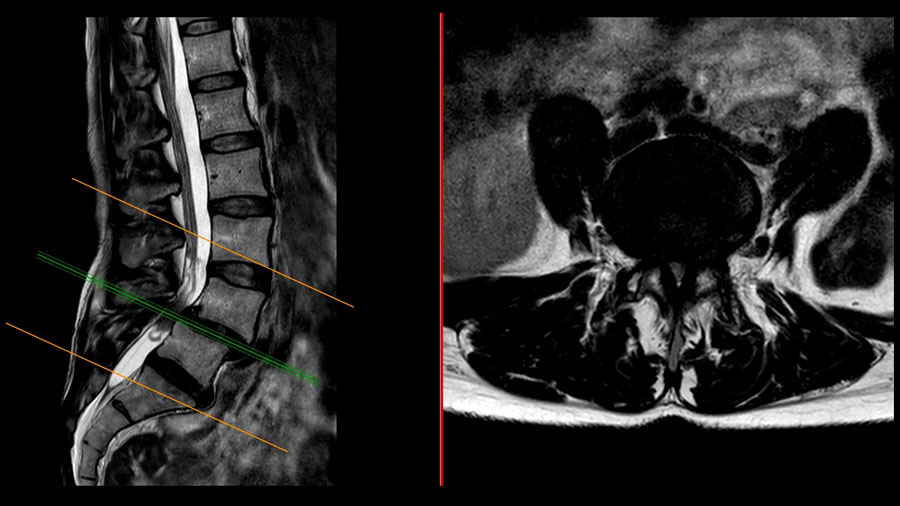

A central concept emphasized in the discussion was concordance, i.e., the alignment between clinical symptoms, imaging findings, and functional impairment. In this case, concordance was clear. The patient’s dominant complaint was progressive neurogenic claudication, and MRI demonstrated central and lateral recess stenosis at L4–5. Supine MRI also showed partial reduction of the spondylolisthesis, highlighting the dynamic nature of the pathology.

Although the primary symptomatic pathology was located at L4–5, the L5–S1 disc showed advanced degeneration with a “black disc” appearance on MRI and a complete loss of segmental lordosis. In a patient with such a high pelvic incidence, this finding became pivotal.